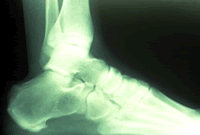

The diagnosis of heel pain and heel spurs is made by a through history of the course of the condition and by physical exam together with weight bearing x-rays. Often an MRI is needed as well. Blood testing is sometimes ordered in order to rule out infection, gout, and or arthritis.

Heel PainOne consequence of this is the development of 1) small tears in the ligament just in front of where it originates on the heel bone, and 2) small tears in the periosteum - "bone skin" - causing the growth of "new bone" and the formation of a heel spur. The pain experienced in the bottom of the heel is rarely if ever from walking on the spur, rather the pain is from the inflammation and irritation to nerves within the plantar fascia and the periosteum, the point where the plantar fascia attaches on the bottom of the heel bone. When the foot rests, the swelling due to inflammation increases. The inflammation is actually the body's attempt to heal itself. But, this inflammation and swelling also puts excessive pressure on nerves, which then only needs a little bit of extra pressure, say from standing on it, to them become extremely painful. People often say that if they walk on the painful heel for 15 to 30 minutes the pain will go away; This is because walking pushes out the swelling that built-up when the foot was resting.